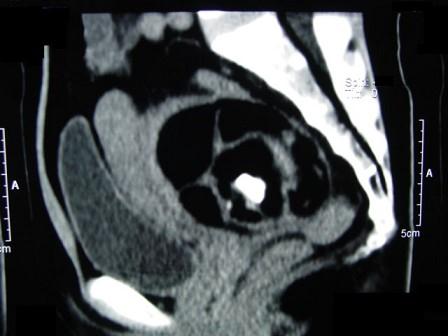

52岁女性患者,因下腹部胀痛就诊,B超提示:盆腔占位,行CT扫描,如图所示盆腔内见囊实性肿块,其内CT值不均,从-120至300hu不等,最可能的诊断为 ...

问题 52岁女性患者,因下腹部胀痛就诊,B超提示:盆腔占位,行CT扫描,如图所示盆腔内见囊实性肿块,其内CT值不均,从-120至300hu不等,最可能的诊断为 ( )

选项 A、卵巢囊肿 B、卵巢粘液瘤 C、盆腔结核 D、子宫肌瘤 E、盆腔畸胎瘤

答案 E